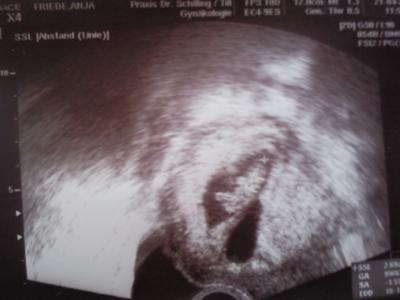

Hatte heute meinen 2 FA termin und dem Zwerg geht es prima. Größe; 2,65 cm SSW 9+6 (nach Größe berechnet) Allerdings ist auch ein 2. Fruchthülle zusehen. jedoch ohne Inhalt. Wissen nicht ob das nur ein Windei ist oder ob das die Blutung war letzte Woche und der Zwilling somit abgegangen ist. Hab jetzt natürlich angst um meinen Zwerg, Der nächste Termin ist am 12.05. freu mich schon drauf :) Hier noch ein US-Bild

Bild zu Bericht FA- Termin - Forum für November - Mamis